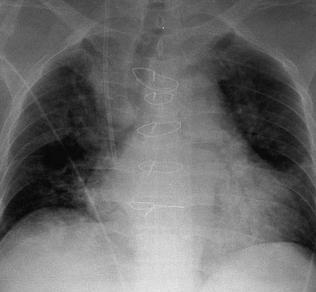

La congestión pulmonar se trata de una acumulación de sangre en los vasos pulmonares. Las causas de su aparición de deben a esfuerzos más o menos violentos, emociones, el aire o gases muy calientes como por ejemplo un incendio o bien el aire gélido. Otras causas son el enfriamiento de los pies, la supresión de la regla menstrual, obstáculos circulatorios, deformaciones torácicas o una alimentación tóxica.La congestión pulmonar especialmente la aguda, puede dar lugar a un edema pulmonar, hemoptisis y apoplejías pulmonares.Los síntomas que presenta el paciente son ligera disnea, opresión en el pecho, ligera fiebre y expectoración acuosa que a veces se acompaña con hilillos de sangre.